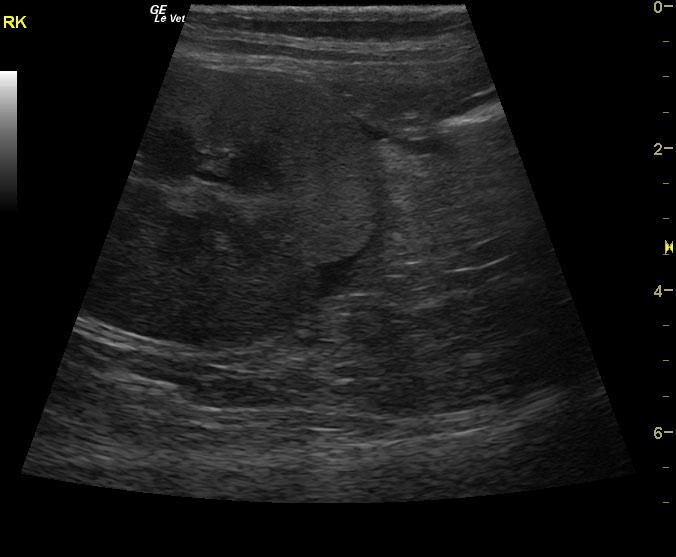

A 15 year old spayed female DMH cat was presented for progressive disease over a 6-8 month period, characterized by poor coat quality, decreased mobility, reduced activity, and pruritic skin lesions that have not responded to antibiotics and use of an E-collar. Abnormalities on physical examination were alopecia, hyperpigmentation, and thinning of the skin of the ventrum, and a non-healing, plaque-like, superficial skin lesion on the cranial aspect of the left stifle and accessory pad of the left carpus. Skin biopsies were scheduled. On urinalysis an inappropriate SG and proteinuria was present with a urine protein: creatinine ratio of 0.3. Abnormalities on serum biochemistry included hypercalcemia and hyperproteinemia. Radiographs showed arthritis of elbow, LS junction, and hips, as well as a mass in the region of the left kidney.